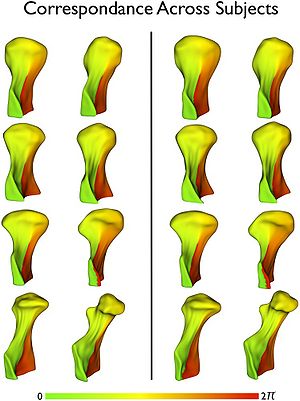

- 3.17 Isometric Scaling in Developing Long Bones Is Achieved by an Optimal Epiphyseal Growth Balance